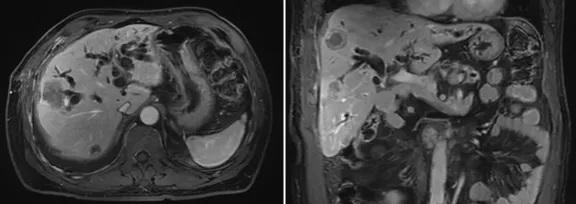

患者12月入院檢查結(jié)果

增強(qiáng)CT結(jié)果

壺腹部腺癌術(shù)后改變,左右肝管匯合部異常信號(hào),不除外復(fù)發(fā)可能;考慮肝內(nèi)多發(fā)轉(zhuǎn)移瘤形成

所見(jiàn)右側(cè)胸腔積液,右下肺片狀異常信號(hào),建議進(jìn)一步胸部檢查